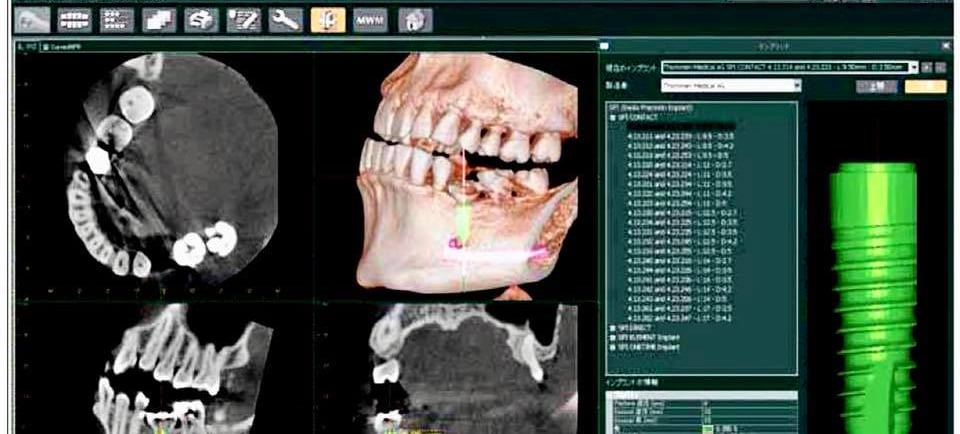

Mistake 3: Ignoring Bone and Soft Tissue Evaluation

Implants depend on:

Bone quality

Bone quantity

Gum health

Ignoring these factors leads to early or late implant failure.